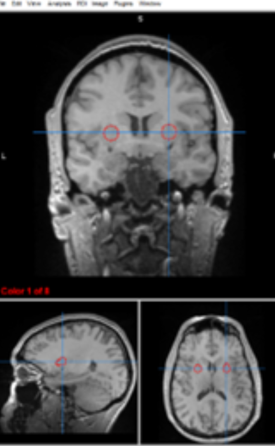

amygdalae

emotional processing, fear conditioning, and memory